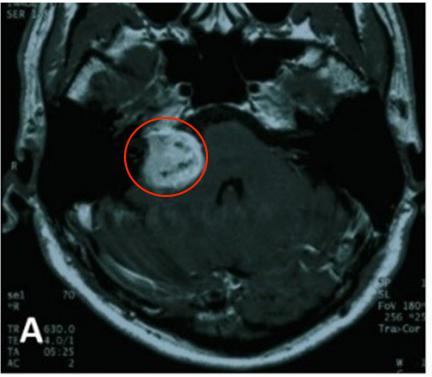

最初的MR影像,轴为钆剂增强T1加权MR影像显示右侧小脑桥角肿瘤异质性强化,肿瘤侵袭右侧内耳道(IAC),怀疑前庭神经鞘瘤。

图1. A.2004年4月最初等 MR图像,轴位钆剂(Gd)增强T1加权MR图像显示右侧小脑桥角肿瘤不均匀强化。

B.在2005年8月1日第一次手术后SRS治疗之前的轴位钆剂(Gd)增强T1加权图像MR图像。

2004年5月,采取右侧乙状窦后入路切除肿瘤。术中肿瘤质地坚实(solid),血管相对丰富,易出血,部分切除肿瘤(图1A-B),于2005年8月行伽玛刀放射外科治疗(GKS)(图2)以控制当时的残留肿留。2007年5月行第二次手术切除,因蛛网膜边缘不清,与面听神经和后组颅神经粘连严重,残留部分肿瘤囊壁(图1C-D)。病人每6个月定期随访脑部MRI(图1E-I),最初的残留肿瘤的大小是稳定的。2013年11月,常规随访MRI显示肿瘤开始生长(图1J)。2014年4月出现进行性头痛、眩晕、和恶心,MRI显示肿瘤肿块增大。2014年6月(图1K-L)进行次全肿瘤切除,术中发现显示,肿瘤有两个部分,也就是说,有一部分是软的且相对容易切除,另一部分有弹性伴有纤维组织,蛛网膜边界不清楚,与面听神经和后组颅神经严重粘连。本病例的第二次及第三次手术均由同一位神经外科医生完成。